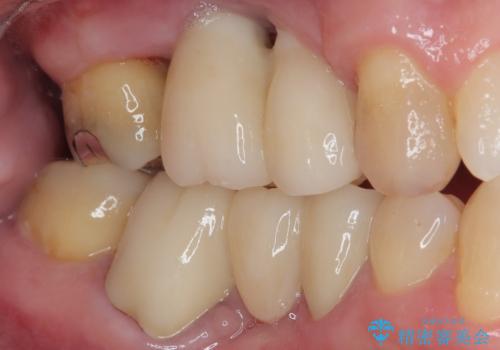

欠損の多い奥歯 インプラントによる補綴治療

右下の銀歯も気になるとのことで、インプラント治療と並行してオールセラミックによるブリッジ補綴治療も行うこととしました。

地元に戻られる前に無事に治療を終えることができました。

今後は東京出張のタイミングでメインテナンスに通院していただきながら、インプラントの状態をチェックしていくことになります。